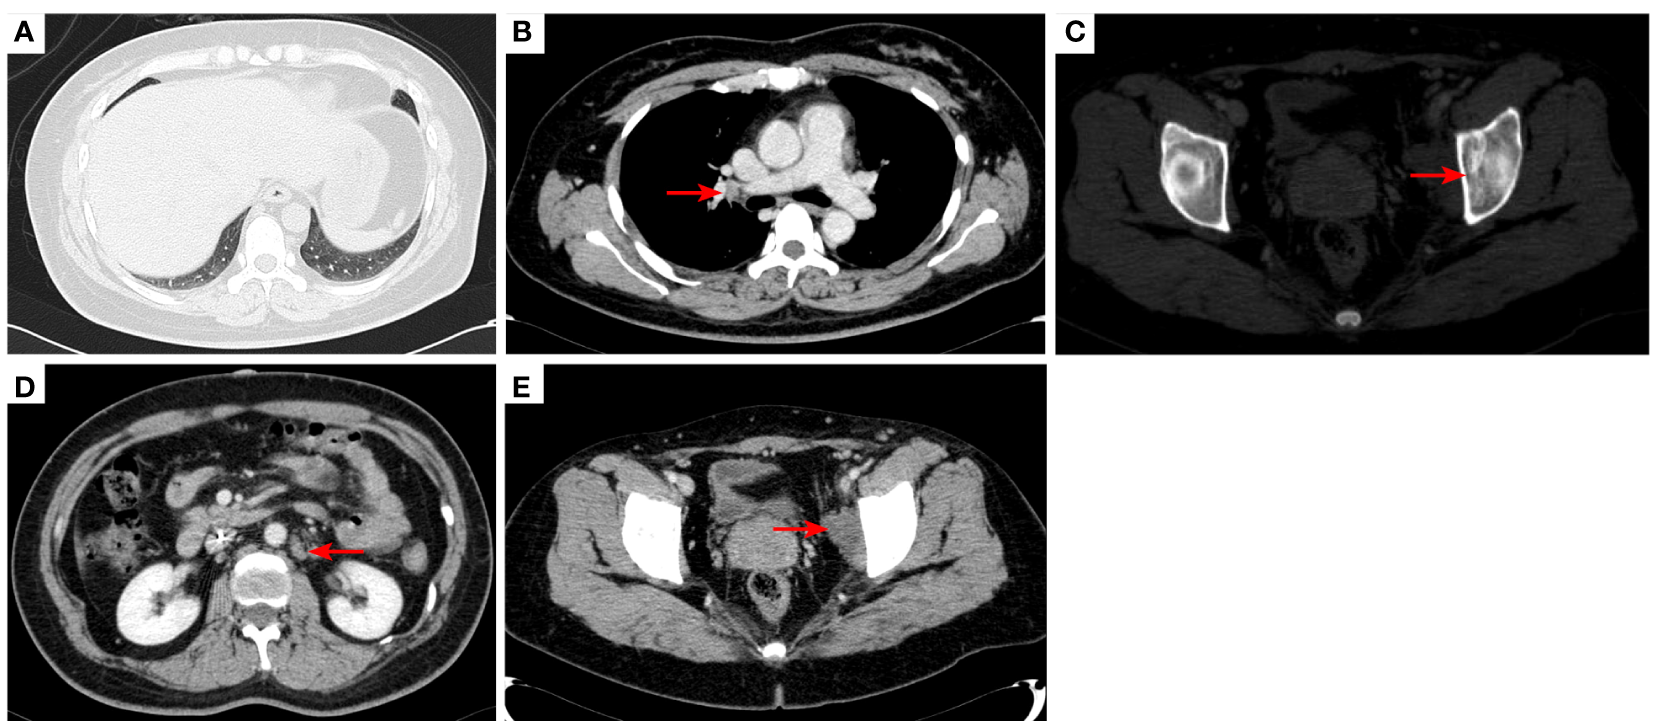

Figure 2

2020–7-10 CT scan: the metastatic tumor in the right lower lobe of the lung and the long diameter was 0.69 cm [red arrow, (A)]. Mediastinal lymph nodes were not significantly enlarged (B). Left acetabular metastases [red arrow, (C)]. Abdominal and abdominal lymph nodes were not significantly enlarged (D) No enlarged lymph nodes were found in the right hilum and the retroperitoneal area. The left pelvic lymph nodes were found and the short diameter was 4.05cm [red arrow, (E)].